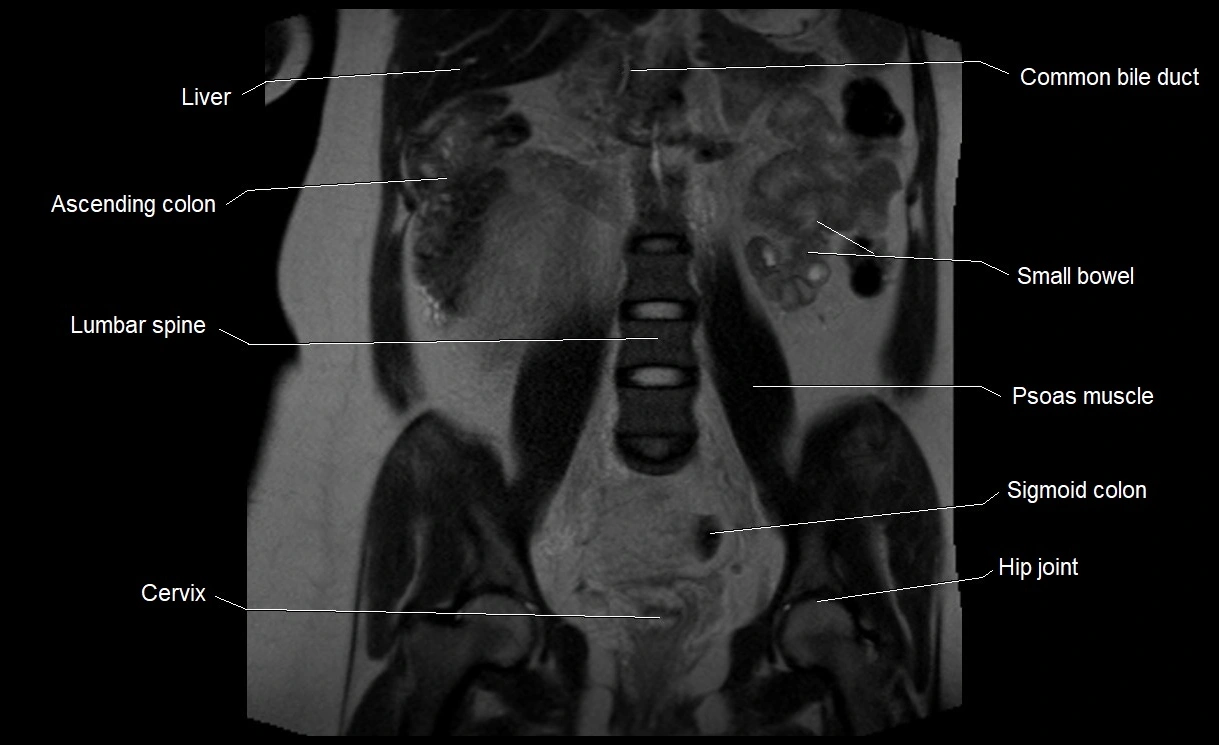

Relations

• Enclosed within the amniotic sac, bounded by the amnion and chorion

• Surrounds and cushions the developing fetus

• In continuity with maternal circulation through placental and transmembrane exchanges

• Imaging relevance: MRI used for fetal visualization and assessing oligohydramnios/polyhydramnios when ultrasound is inconclusive